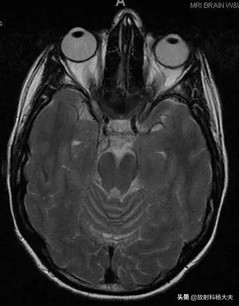

又或者每天被患者以轴位翻无数个白眼。。。。